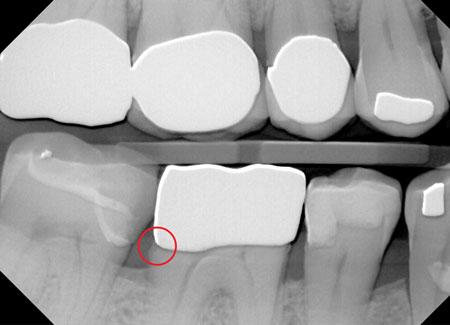

Figure 2: Proximal contact adjustment is simpler than ever and vital to the care patients expect.

When restoring interproximal relief-the natural, comfortable, passive contact or microscopic clearance between teeth-there is fortunately an easier and far more accurate way to adjust proximal contacts. Using a thin (0.06 mm or less), single-handed, single-sided diamond strip, we can perform necessary adjustments intraorally and without articulating films and rotary instruments. After placing the crown on the prepared tooth and noting the contact intensity and marginal fit, the diamond strip is simply passed buccolingually through both the mesial and distal interproximal spaces until equal light resistance is felt (figure 2). This ensures complete marginal seating and a far more satisfying patient experience.

Figure 3: Perfect proximal contacts and complete marginal seating help ensure happy patients who return to your practice.

Ultimately, the best interests of both the dental professional and cost-conscious small-business owner in all of us are perfectly aligned. As is often the case, the optimal strategy to ensure the success of your practice is to provide the best care and experience to each patient. With ideal proximal contact adjustment, this truth is particularly clear. The choice to make is whether your proximal contact adjustments will cost you a minute or two and some pocket change, or potentially cost you a patient and thousands of dollars (figure 3).